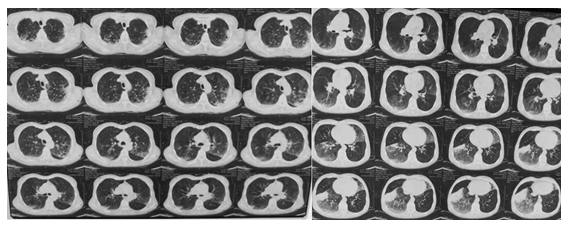

老年女性患者,64岁,因“间断咳嗽、咳痰50年,加重伴发热10 d”于2017年9月13日入院。患者于50年前吸烟后间断出现咳嗽、咳痰症状,每年冬春季节好发,抗炎对症治疗后好转,病情时好时坏;10 d前出现发热,体温最高达38.5℃,多于午后发热,伴畏寒、乏力、出汗、咳嗽,呈阵发性,咳胶冻样黄痰,量多,活动后胸闷、气短,无胸痛,无痰中带血,就诊于当地医院,胸部CT提示双肺多发斑片影(图1),给予“哌拉西林他唑巴坦”治疗8 d后,复查胸部CT提示双肺弥漫性病变,其内并有间质性改变进一步加重(图2),为求进一步治疗转入我院。病程中无腹痛、腹泻,无尿路刺激症状,近期体重无明显增减。

图1 胸部CT:双肺多发斑片影

图2 复查胸部CT:双肺弥漫性病变,间质性改变进一步加重